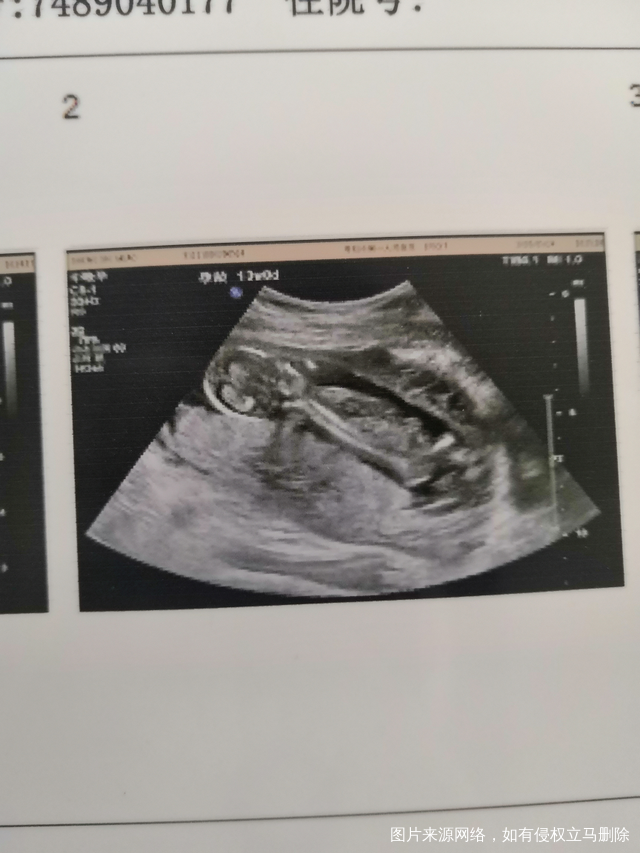

有没有经验帮忙看看性别,

第一个是儿子,这胎想要女儿[冒心心]忘有经验的分享下经验,给点勇气,谢谢😜